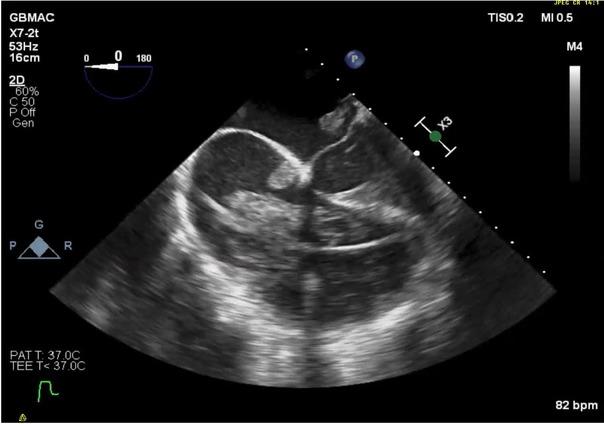

The possibility of acute myocardial infarction (MI), likely in the right coronary artery (RCA) distribution region, was considered. TEE video clips demonstrate clots located in all four chambers (Figure1; Online supplementary video 1); a massive clot in mitral position on the biplane view (Figure 2; Online supplementary video 2); and clots in both ventricles, as demonstrated on Figure 3 (Online supplementary video 3), that also showed that right ventricular outflow tract (RVOT) inflow-outflow was almost obstructed with a clot in AV.

Fig. 1

Clots located in all four chambers